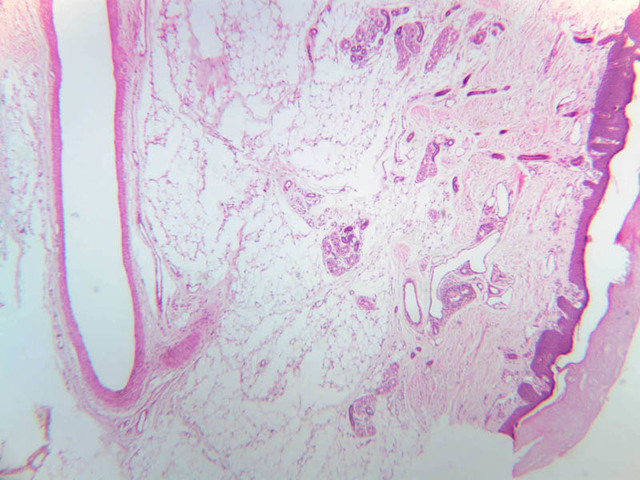

Blood passes from the elastic arteries via arteries of intermediate type into the muscular (distribution) arteries. Locate and examine a muscular artery in slide A-28 (Renal artery & vein, H&E [2.5x, 10x-labeled, 20x, 40x-labeled] [10x-labeled, 20x, 40x]; AF [10x-labeled, 20x, 40x]). Note that the tunica intima is separated from the tunica media by a thick internal elastic membrane which has a scalloped appearance. The tunica media consists of many layers of smooth muscle cells arranged concentrically in a spiral fashion (A-28, H&E [2.5x, 10x-labeled, 20x, 40x] [2.5x, 10x, 20x, 40x, 40x] [2.5x, 10x, 20x]). An external elastic membrane is present, but is thinner and less complete than the internal elastic membrane. The tunica adventitia is about equal in size to the media in this vessel and is more intensely eosinophilic in its staining properties. Note the appearance of small blood vessels in the outer part of the tunica adventitia. You may also be able to see occasional nerve fibers.